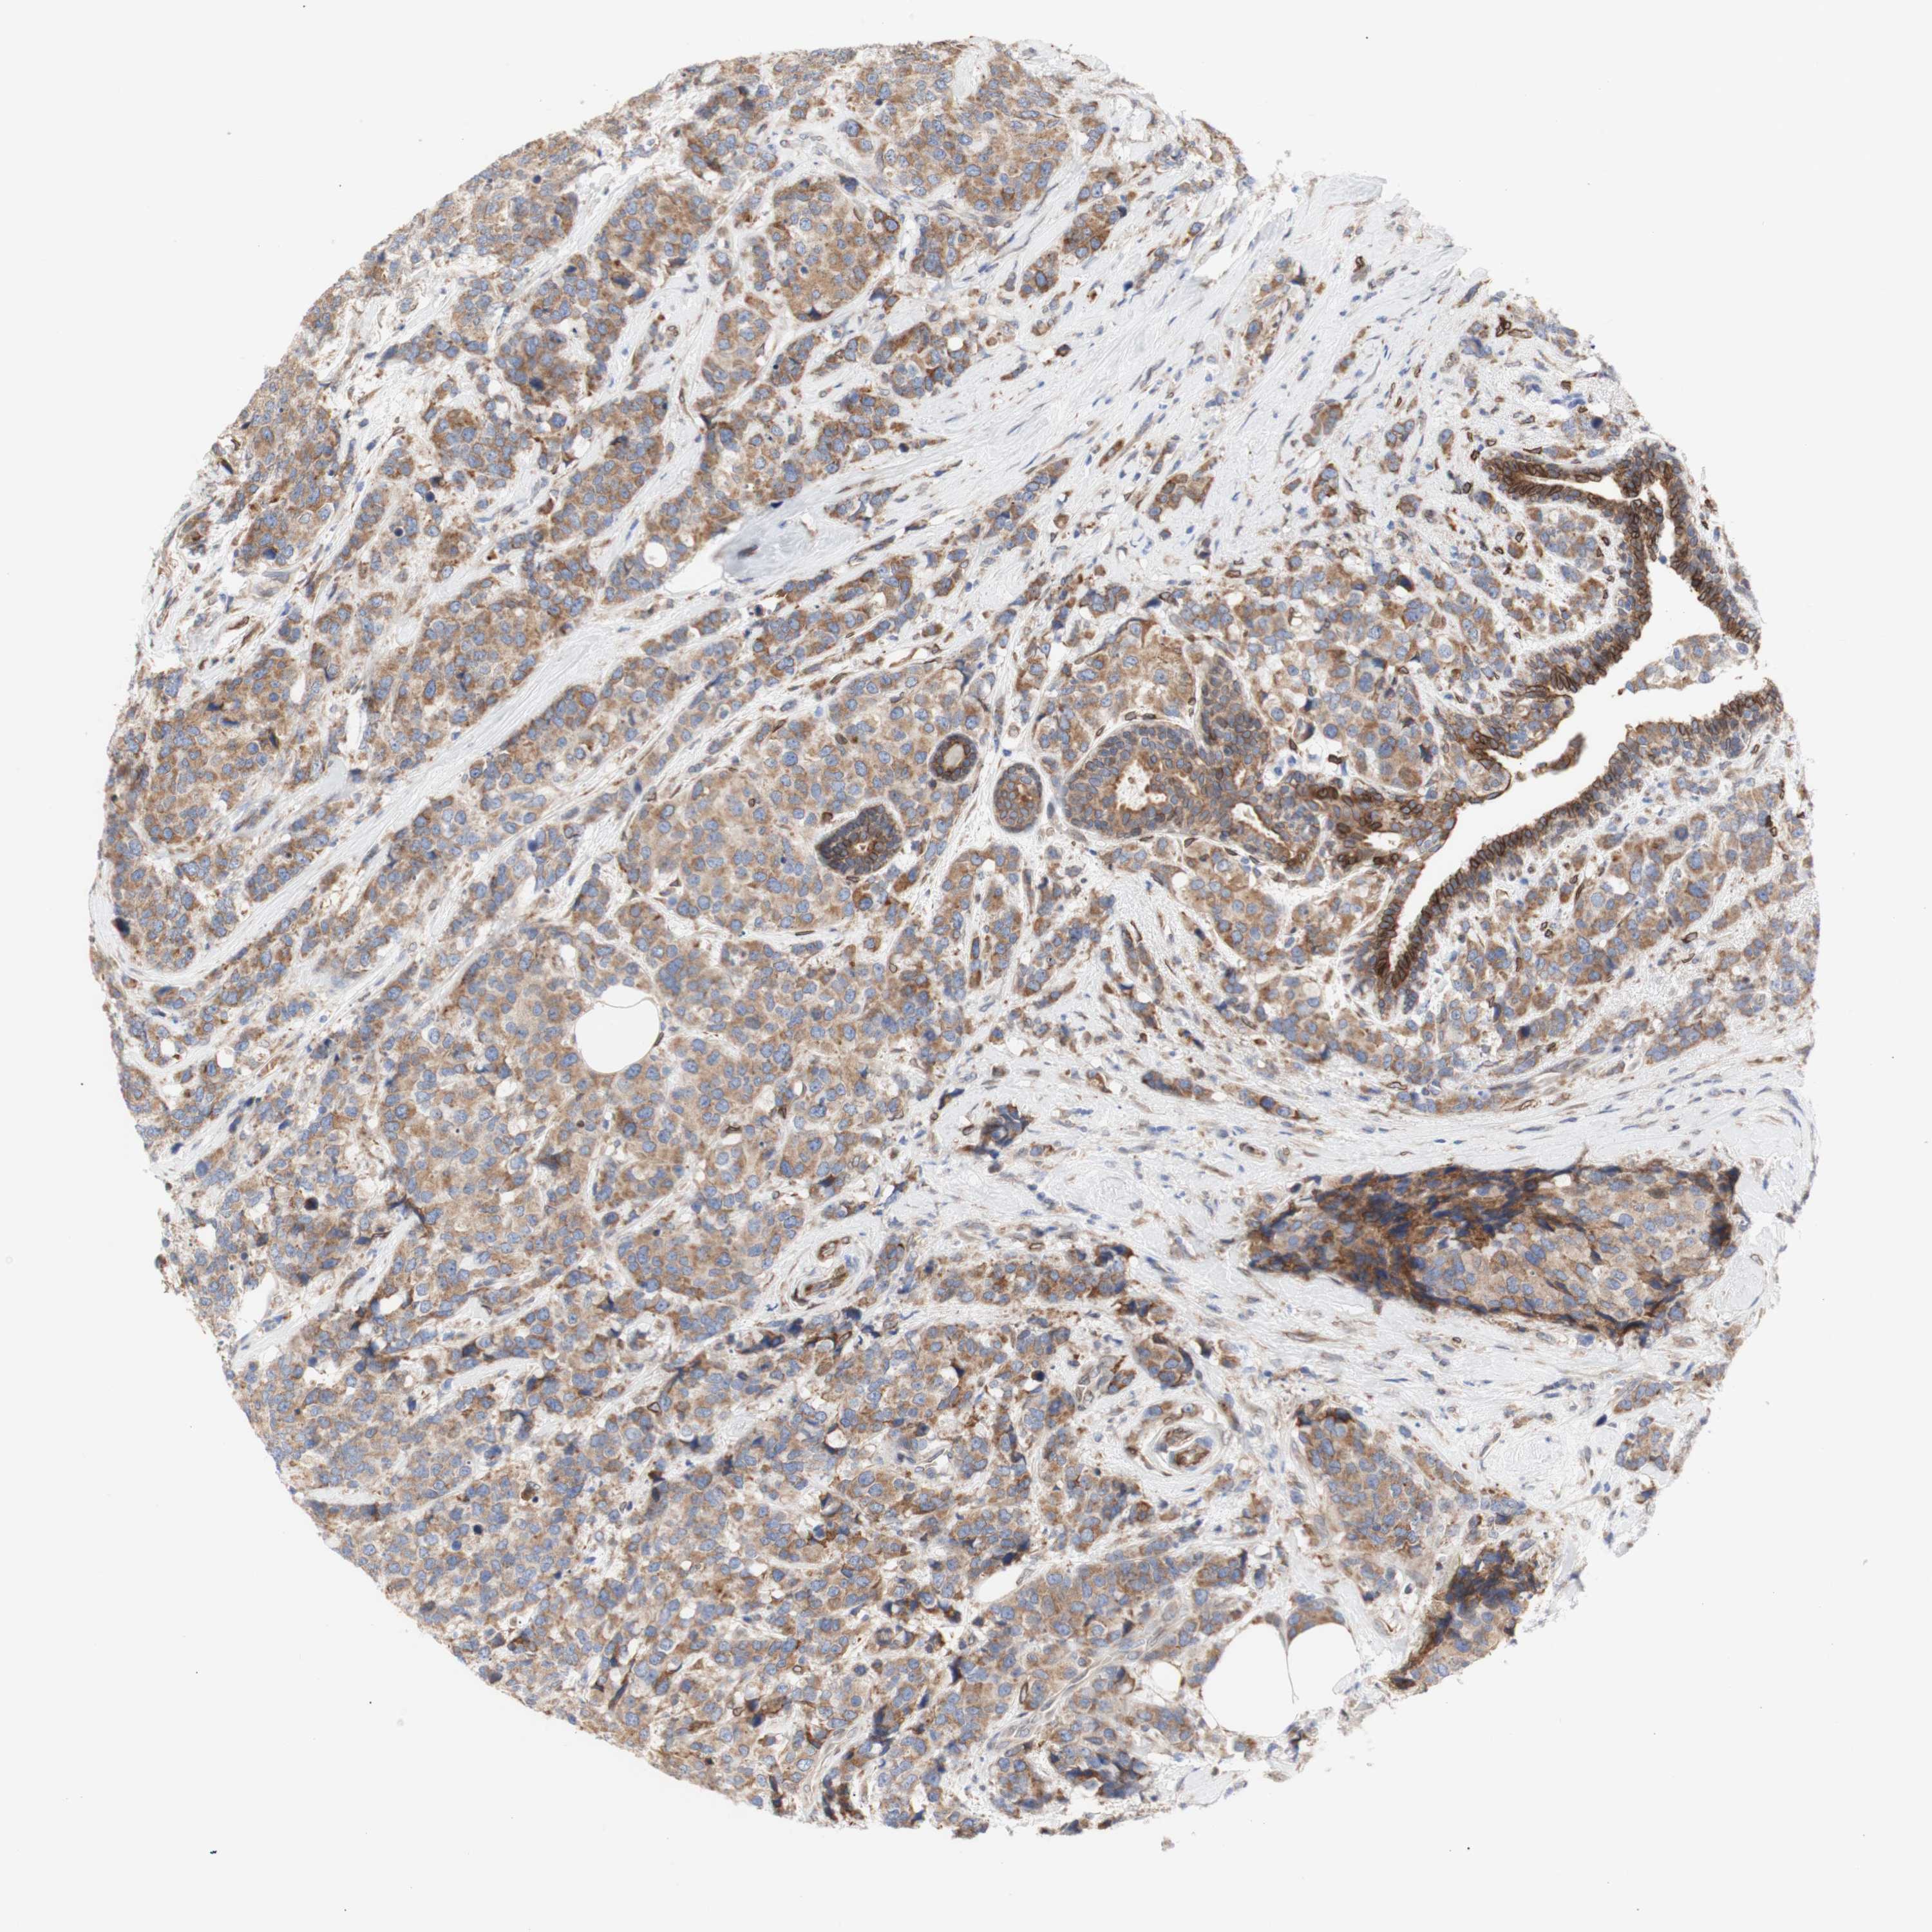

CANCER BREAST CANCER Show tissue menu

BRCA TCGA BRCA VALIDATION PROTEIN EXPRESSION